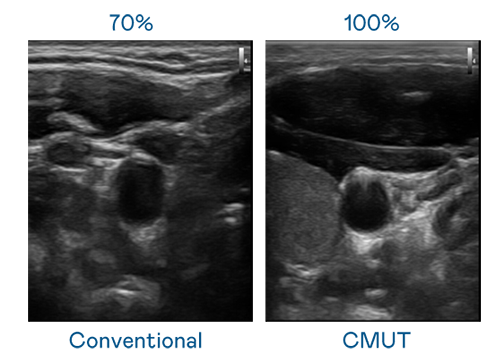

CMUT 技术是一种用电容式微机电元件来产生超音波讯号的技术。与传统 PZT 压电式技术相比,CMUT 频宽增加 30%,更宽频的超音波讯号让影像解析度大幅提升,是实现高影像品质医疗超音波扫描、促进精准医疗发展的关键技术。

大频宽带来超清晰影像

超音波影像的解析度高低,首先取决于探头能发出的讯号频宽。初恋时间动漫1-6集免费观看 CMUT 可提供高清晰的超音波讯号,提供高频宽、高灵敏度、影像纹理细节更高的超音波影像,协助医护人员缩短影像判读时间及利用精准的医疗影像进行诊断。